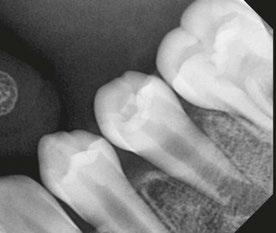

Figure 5 (left): Collagen tape was placed directly over the blood clot. Figure 6 (center left): Bioceramic putty was placed directly over the collagen tape. Figure 7 (center right): Periapical radiograph showing the placement of the bioceramic putty in the canal. Figure 8 (right): Restored access

Figure 9 (left): Immediate postoperative periapical radiograph of tooth No. 20. Figure 10 (right): 6-month recall CBCT scan showing no evidence of apical periodontitis and a calcific barrier forming mid-root